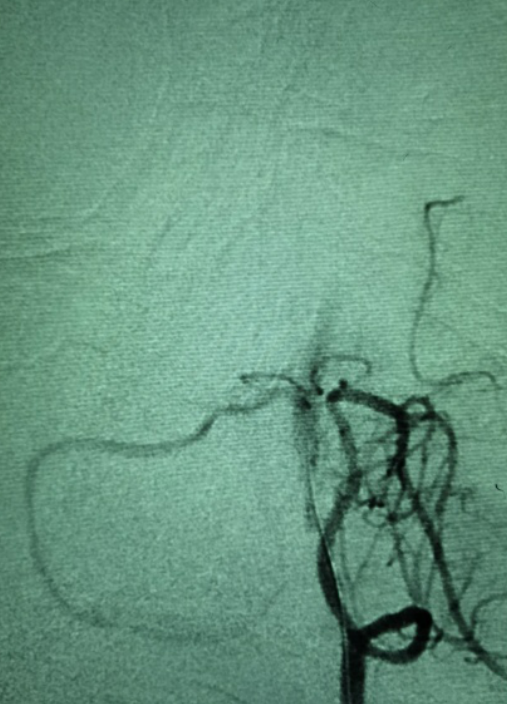

全脑血管造影提示右椎纤细,颅内段不显影。左椎颅内段发出小脑后下动脉已远闭塞,但部分血管吻合,使左椎V4远端浅淡显影。

前循环造影提示后交通开放,基底动脉逆向显影,基底动脉中下段血管床未显影。

5F 115cm远端通路导管超选至左侧椎动脉V3段,选取术中工作角度造影。